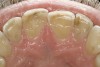

The teeth themselves often can be full of diagnostic information. Is there excessive tooth wear (Figure 7 through Figure 9)? Is there excessive mobility in any teeth? Is there unwanted migration of teeth? Is there a centric relation/maximum intercuspation discrepancy (hit on inclines and slide into full intercuspation) (Figure 3)? If there is a discrepancy, is the deviation in the arc of closure or line of closure? Is the patient able to chew all types of food on both sides without pain? Does the patient feel like their bite is changing or unstable? In addition, are there functional patterns evident by the wear present on the teeth. For instance, horizontal bruxers (Figure 10) often have flat tabletop wear present. Vertical, constricted wear patterns (Figure 11) often have anterior chipping and lingual wear of maxillary anterior teeth.

CLINICAL EXAMPLES (7.) Teeth Nos. 4 through 6 were loaded excessively in lateral movements; tooth No. 5 was the first tooth to hit in the CR arc of closure. (8.) An example of excessive lingual tooth wear in a patient with a restricted envelope of function.

Figure 7  CLINICAL EXAMPLES Teeth Nos. 4 through 6 were loaded excessively in lateral movements; tooth No. 5 was the first tooth to hit in the CR arc of closure.

Figure 7

Figure 8  CLINICAL EXAMPLES An example of excessive lingual tooth wear in a patient with a restricted envelope of function.

Figure 8